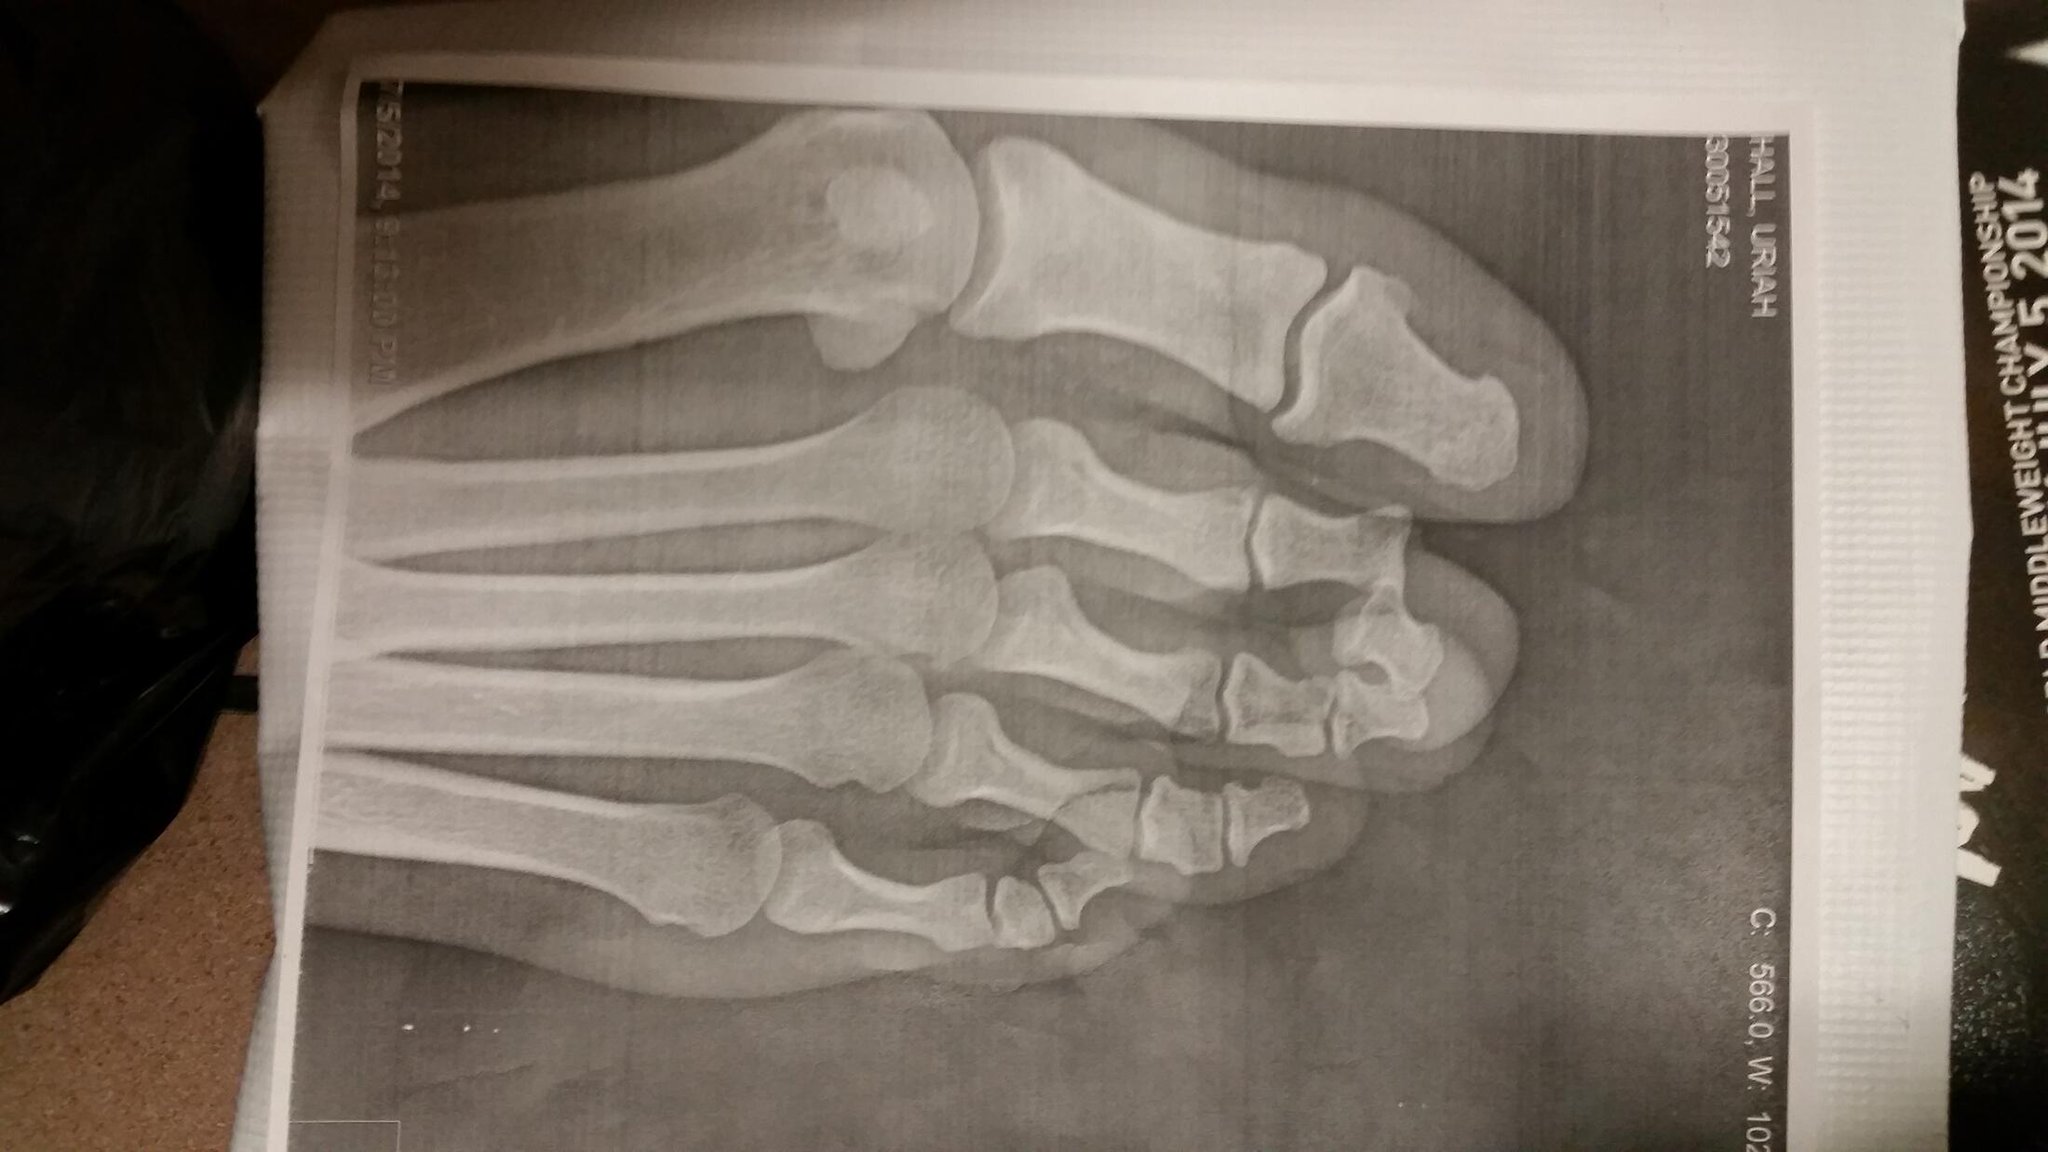

Even if Uriah never reaches his potential, I will be a fan. It was a brutal fight to watch, knowing how mangled his foot was. I hope he makes a full recovery and is back soon.